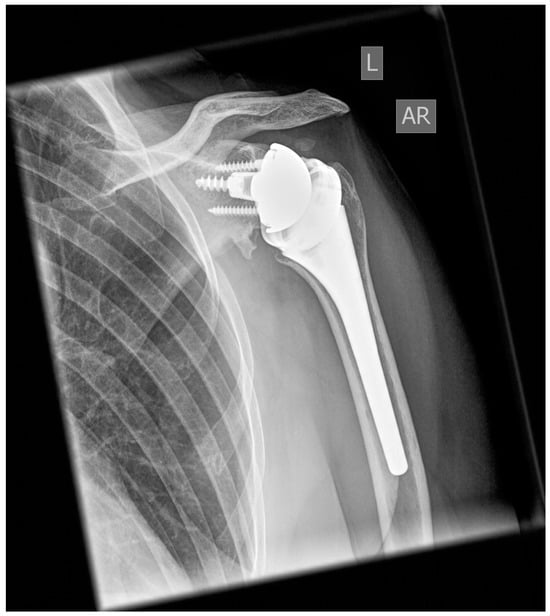

All patients were treated with RSA using the Univers Revers prosthesis with a 135° NSA (Arthrex, Naples, FL, USA; Figure 1) combined with the Universal Glenoid (Arthrex, Naples, FL, USA). The design of this prosthesis is based on the usage of a rectangular metadiaphyseal locking stem that is combined with a metaphyseal cup which be used centered or with either 2 mm left or right offset according the humeral diaphysis. This humeral inlay design is further completed by the usage of a standard or constrained +3 mm or +6 mm humeral polyethylene liner that offers adaptation to the glenosphere diameters’ different concavity depths (jump heights) from 9.8 mm (36 mm standard) to 13.9 mm (42 mm constrained) and following stability ratios of 193–194% using a standard liner as well as stability ratios of 277–300% using constrained liner designs [].

Figure 1.

Example at the five-year follow-up after reverse shoulder arthroplasty with 135° NSA and a cementless metadiaphyseal fixation stem (Univers Revers, Arthrex, Naples, FL).